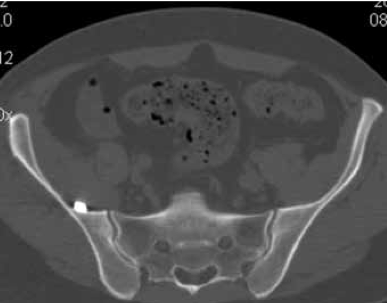

Клинический пример. Пациентка М., 21 год, поступила в клинику через 1,5 месяца после ДТП с диагнозом: ротационно-нестабильное повреждение таза; U-образный перелом крестца с вершиной над SII. Оскольчатый перелом крыла правой подвздошной кости с частичным повреждением правого крестцово-подвздошного сочленения. Радикулопатия S1 справа, S2, S3 с обеих сторон средней степени (Фиг. 1 - обзорная рентгенограмма таза (а); КТ сканы в сагиттальной (б) и горизонтальной (в) плоскости при поступлении).

По предлагаемому способу в одну операционную сессию выполнен:

- остеосинтез крыла подвздошной кости винтами и фиксация U-образного перелома крестца илиосакральным винтом для стабилизации повреждений тазовых костей;

- костнопластическая остеотомия задней стенки крестцового канала, открытая декомпрессия дурального мешка, ремоделирование крестцового канала;

- фиксация ламинектомированного фрагмента по линии остеотомии сетчатой пластиной (Фиг. 2 - представлена обзорная рентгенограмма таза (а) и КТ сканы в сагиттальной (б) и горизонтальной (в) плоскости после операции. После операции пациентка активизирована на третьи сутки, рана заживлена первичным натяжением, швы сняты не 12 сутки. Проводилась медикаментозная и электоронейростимуляция. Выписана из стационара на 17 сутки после операции.